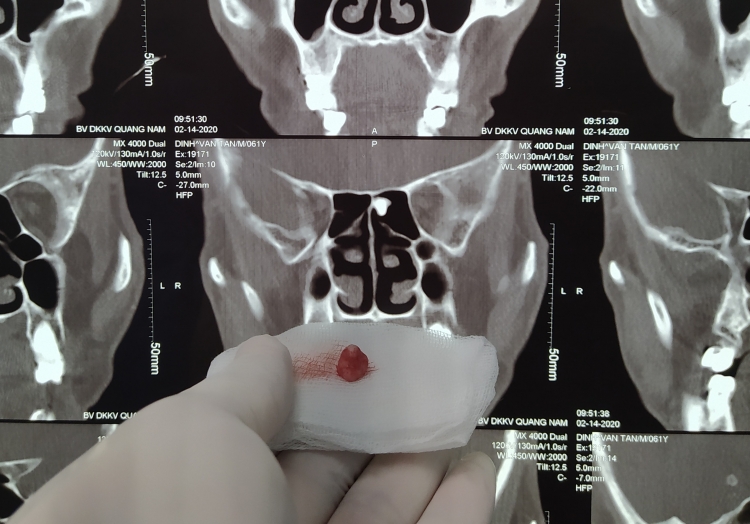

2 cháu bé là Lê Nguyễn Bảo Tr. (5 tuổi, nặng 15kg, trú Quảng Nam) và Hoàng Trần Bảo H. (11 tháng tuổi, nặng 5,5kg, trú Thừa Thiên Huế) bị ung thư nguyên bào gan kích thước khổng lồ đường kính gần 20cm.

Sau khi điều trị với hóa chất làm u nhỏ lại đã được hội chẩn đa chuyên khoa và được chỉ định phẫu thuật cắt gan.

Mặc dù u đã nhỏ hơn so với ban đầu, nhưng vẫn còn chiếm một phần lớn gan, nên cả hai cháu đều được lên kế hoạch cắt gan lớn.